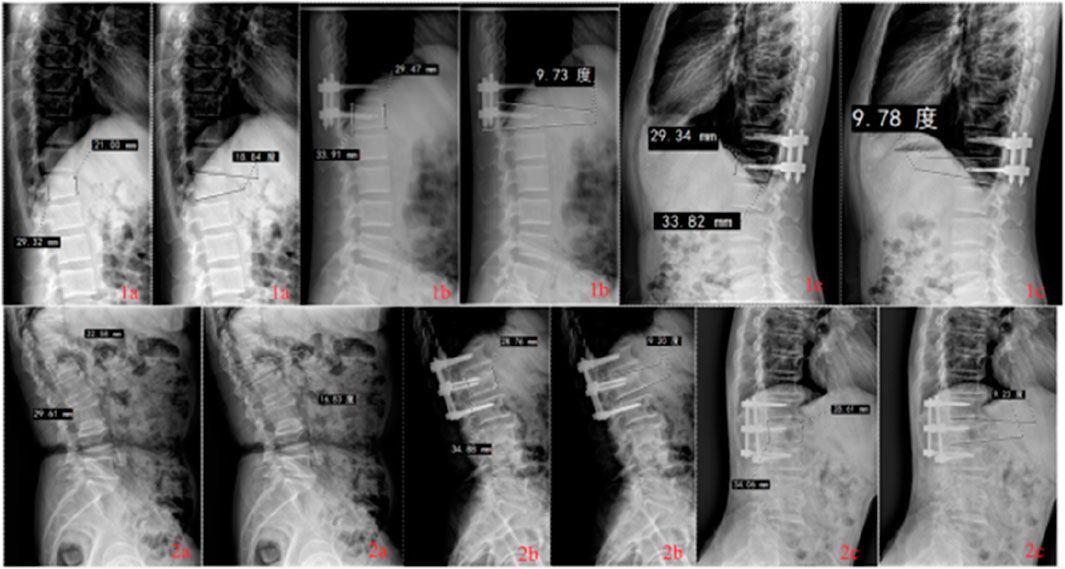

Objective: To compare the finite element analysis and clinical follow-up of posterior 4 pedicle screw mono-segment and 6 pedicle screw short-segment pedicle screw fixation techniques in the treatment of thoracolumbar endplate fractures of the spine. Methods: 1.The finite element method was used to analyze the treatment of thoracolumbar upper endplate or lower endplate burst fractures with posterior 4 pedicle screw mono-segment and 6 pedicle screw short-segment pedicle screw fixation techniques (UM: upper endplate fracture+mono-segment pedicle screw fixation [UEPF+MPSF], US: upper endplate fracture+short-segment pedicle screw fixation [UEPF+SPSF], LM: lower endplate fracture+mono-segment pedicle screw fixation [LEPF+MPSF], LS: lower endplate fracture+short-segment pedicle screw fixation [LEPF+SPSF]). 2.A retrospective analysis was conducted on 77 patients with mild to moderate thoracolumbar spine fractures of type A3.1 admitted from October 2019 to October 2024. Among them, 38 patients underwent posterior 4 pedicle screw mono-segment, and 39 patients underwent posterior 6 pedicle screw short-segment fixation. The perioperative performance, clinical functional performance, and imaging performance were compared between the two groups. Results: 1.Finite element analysis and prediction based on specific models: In fractures of the same type, the range of motion (ROM) in all directions of 4 pedicle screw mono-segment fixation showed a trend of higher values compared with 6 pedicle screw short-segment fixation, while the von Mises stress of adjacent intervertebral discs and adjacent facet joints showed a trend of lower values compared with 6-screw short-segment fixation. The 6 pedicle screw short-segment fixation model predicted that the maximum displacement of the fixed segment, the mobility of the fixed segment, and the mobility of the injured vertebra were smaller than those of 4 pedicle screw mono-segment fixation. The peak von Mises stress values of screws in the US, UM, LS, and LM groups were 386.61 Mpa, 397.60 Mpa, 302.63 Mpa, and 305.59 Mpa, respectively; the peak von Mises stress values of rods in these groups were 416.22 Mpa, 446.18 Mpa, 329.03 Mpa, and 347.47 Mpa, respectively. The stress of the injured vertebra in 6 pedicle screw short-segment fixation showed a trend of lower values compared with 4 pedicle screw mono-segment fixation……